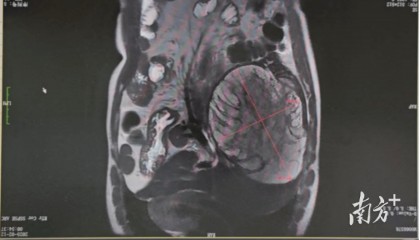

三分之二的肝被切除,他却感叹:像卸下了一块大石头

“切了三分之二的肝,像卸下了一块大石头,我很庆幸捡回了一条命。”患者谢先生(化名)说。近日,广州医科...